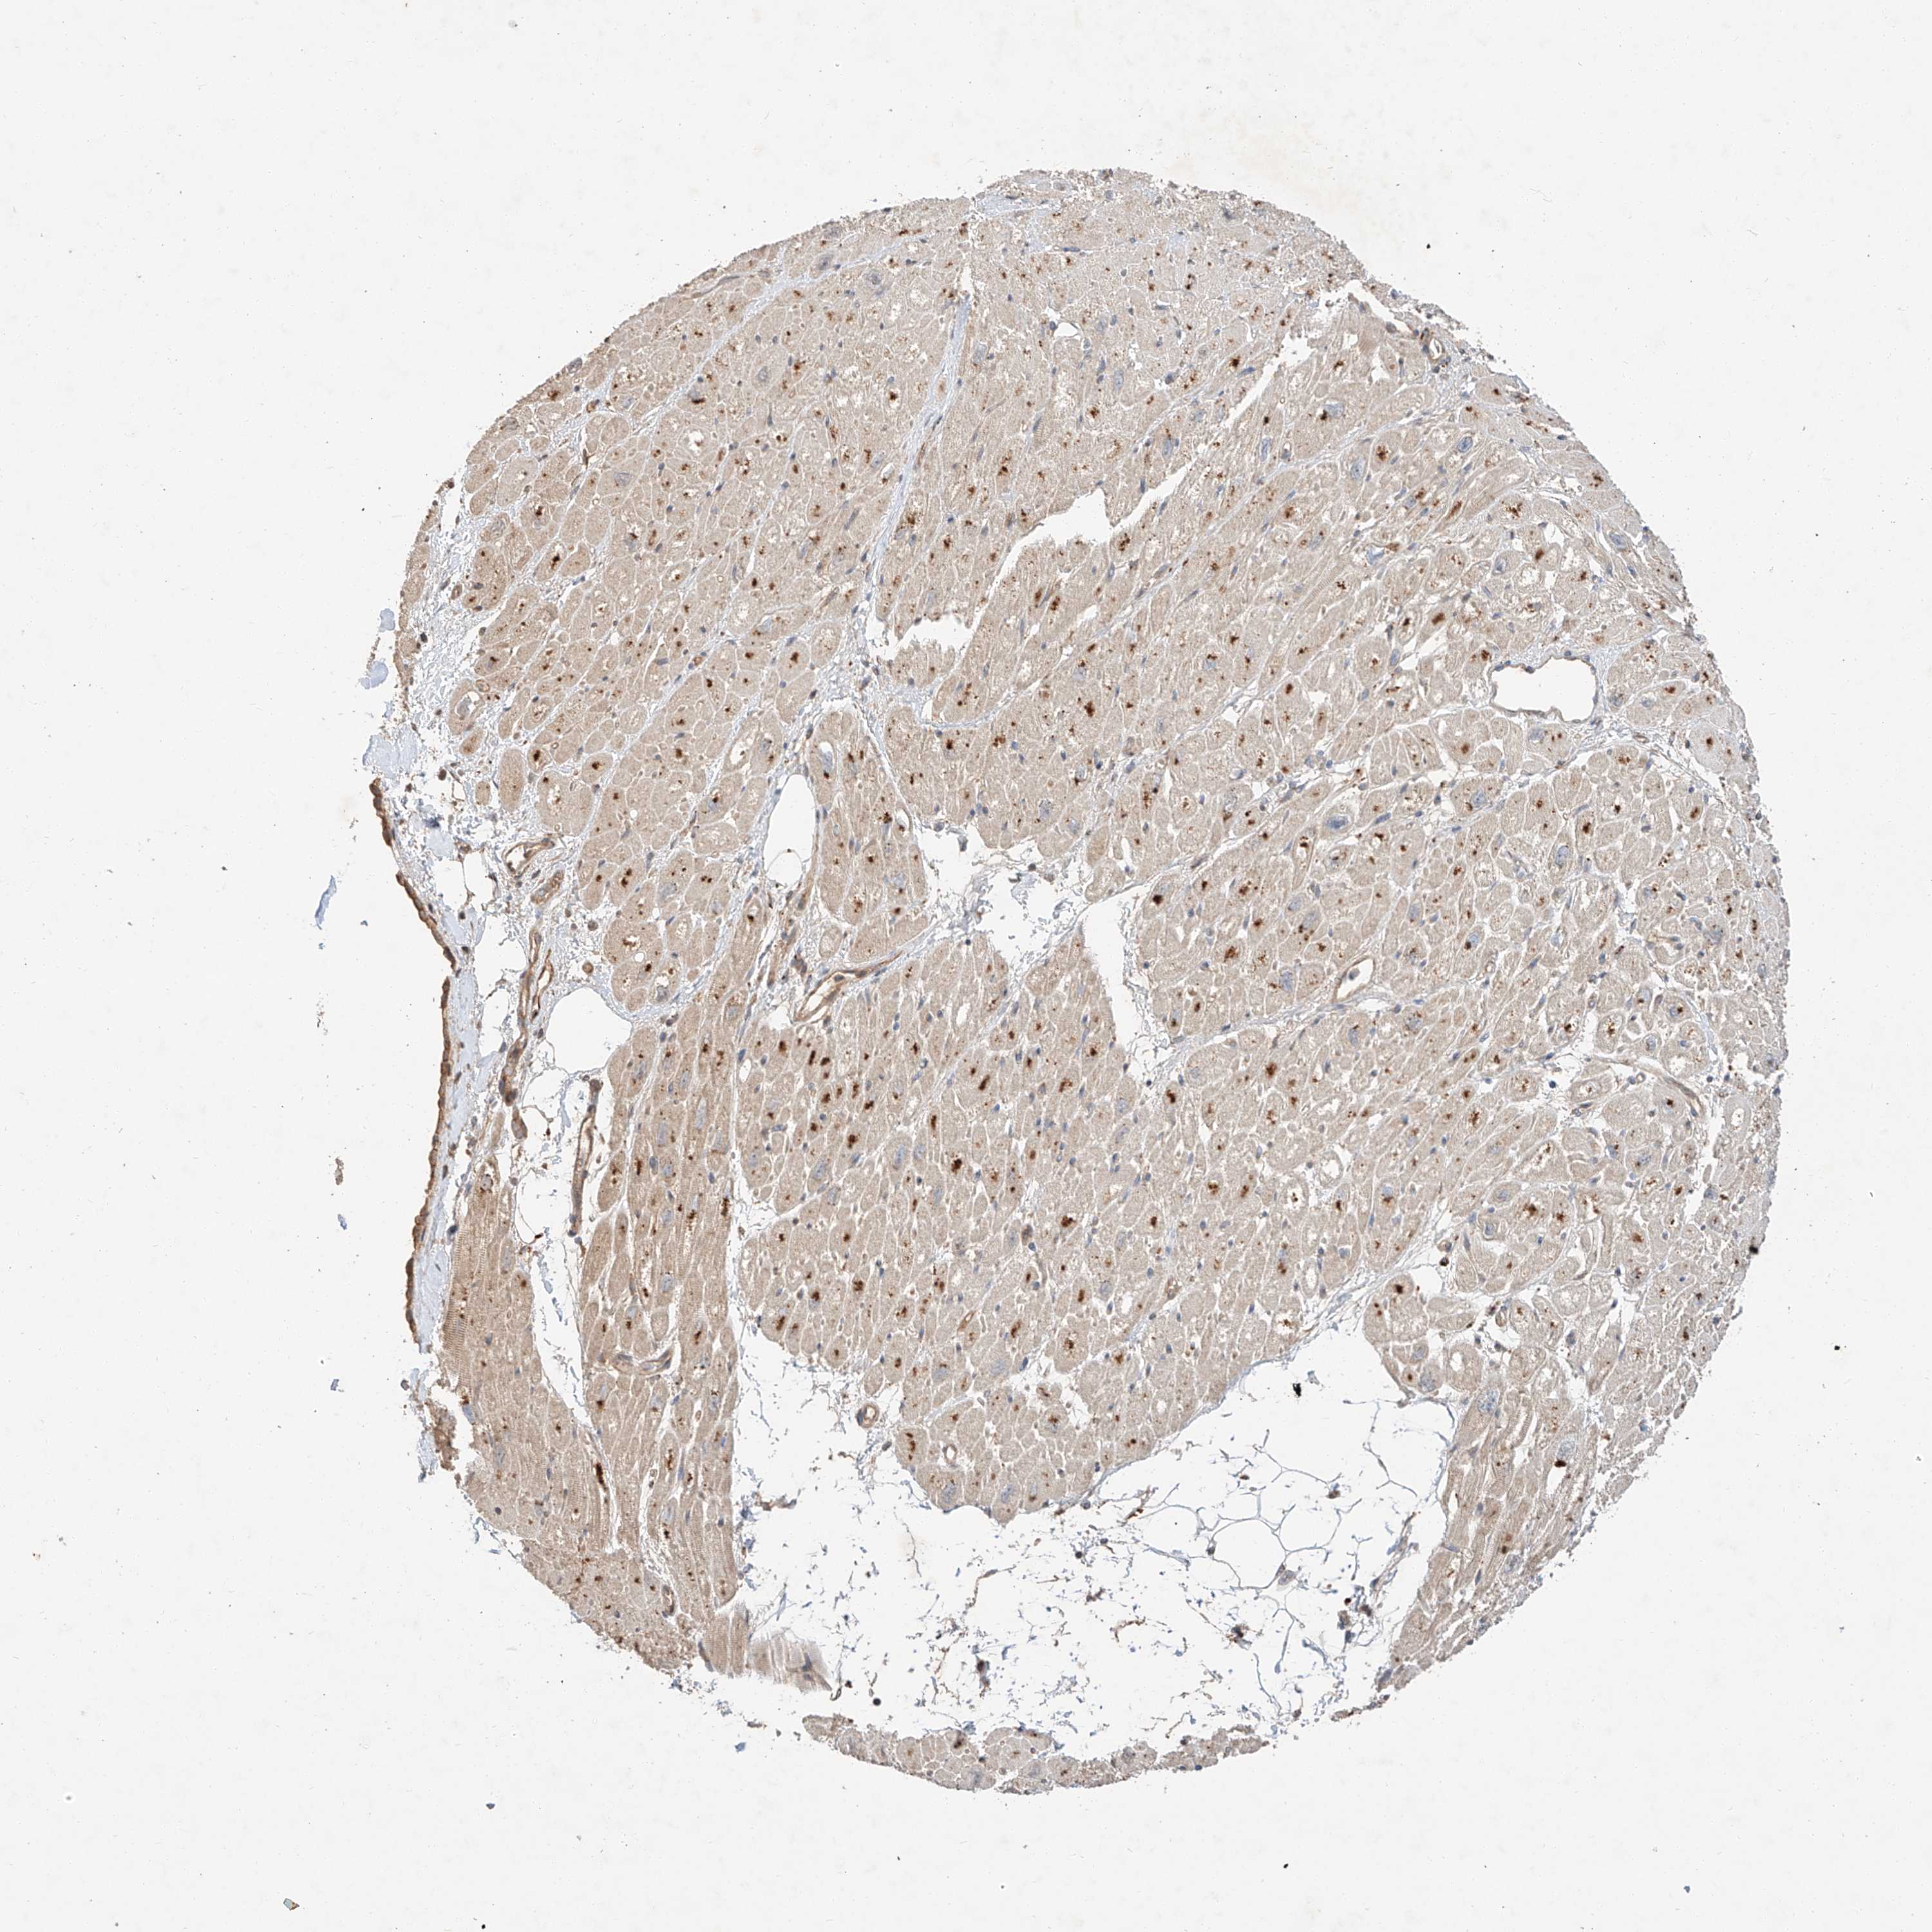

HEART MUSCLE - Antibody stainingi

Antibody staining in the annotated cell types in the current human tissue is reported as not detected, low, medium, or high, based on conventional immunohistochemistry profiling in selected tissues. This score is based on the combination of the staining intensity and fraction of stained cells.

Each image is clickable and will lead to virtual microscopy that enables deeper exploration of all samples and also displays staining intensity scores, fraction scores and subcellular localization as well as patient and tissue information for each sample.

Antibody HPA030464

Cardiomyocytes High